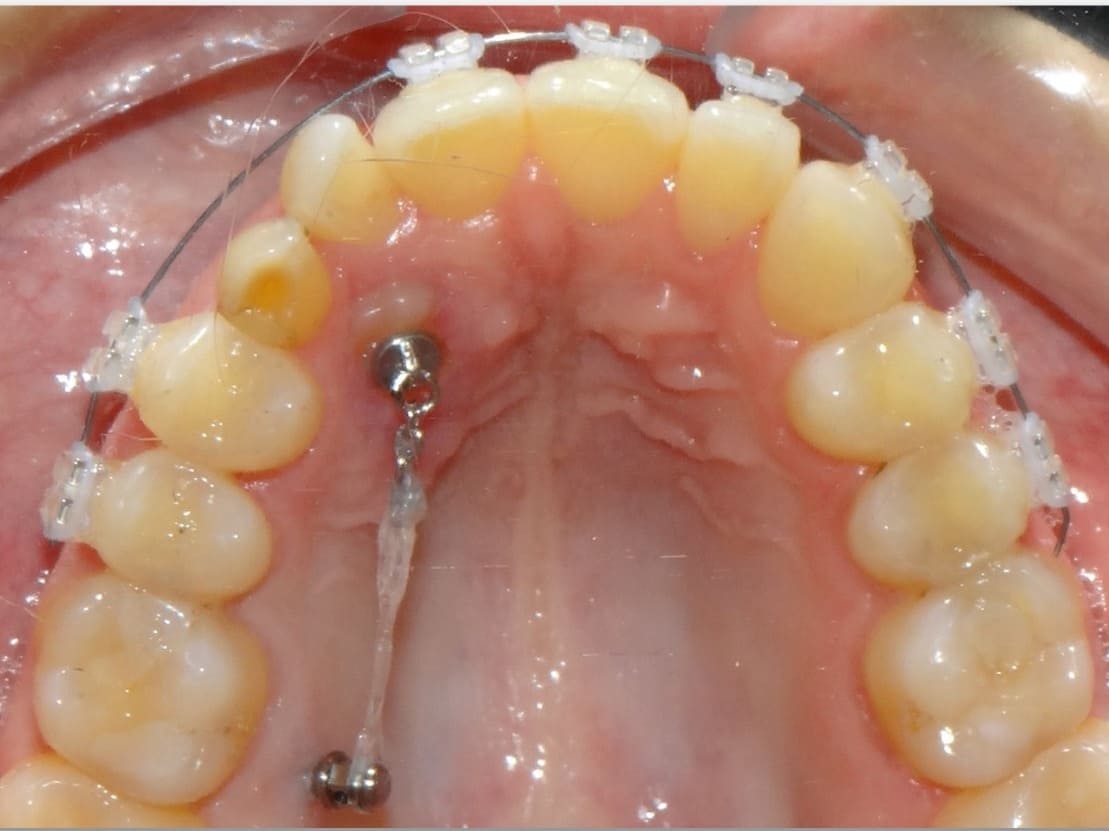

Capacitar o ortodontista quanto a eleger a melhor estratégia biomecânica com o uso de ancoragem esquelética. A abrangência do curso oferecerá conhecimento quanto aos mini implantes intra-alveolares, extra-alveolares, palatino e MARPE, tanto na liga de titânio quanto aço inoxidável